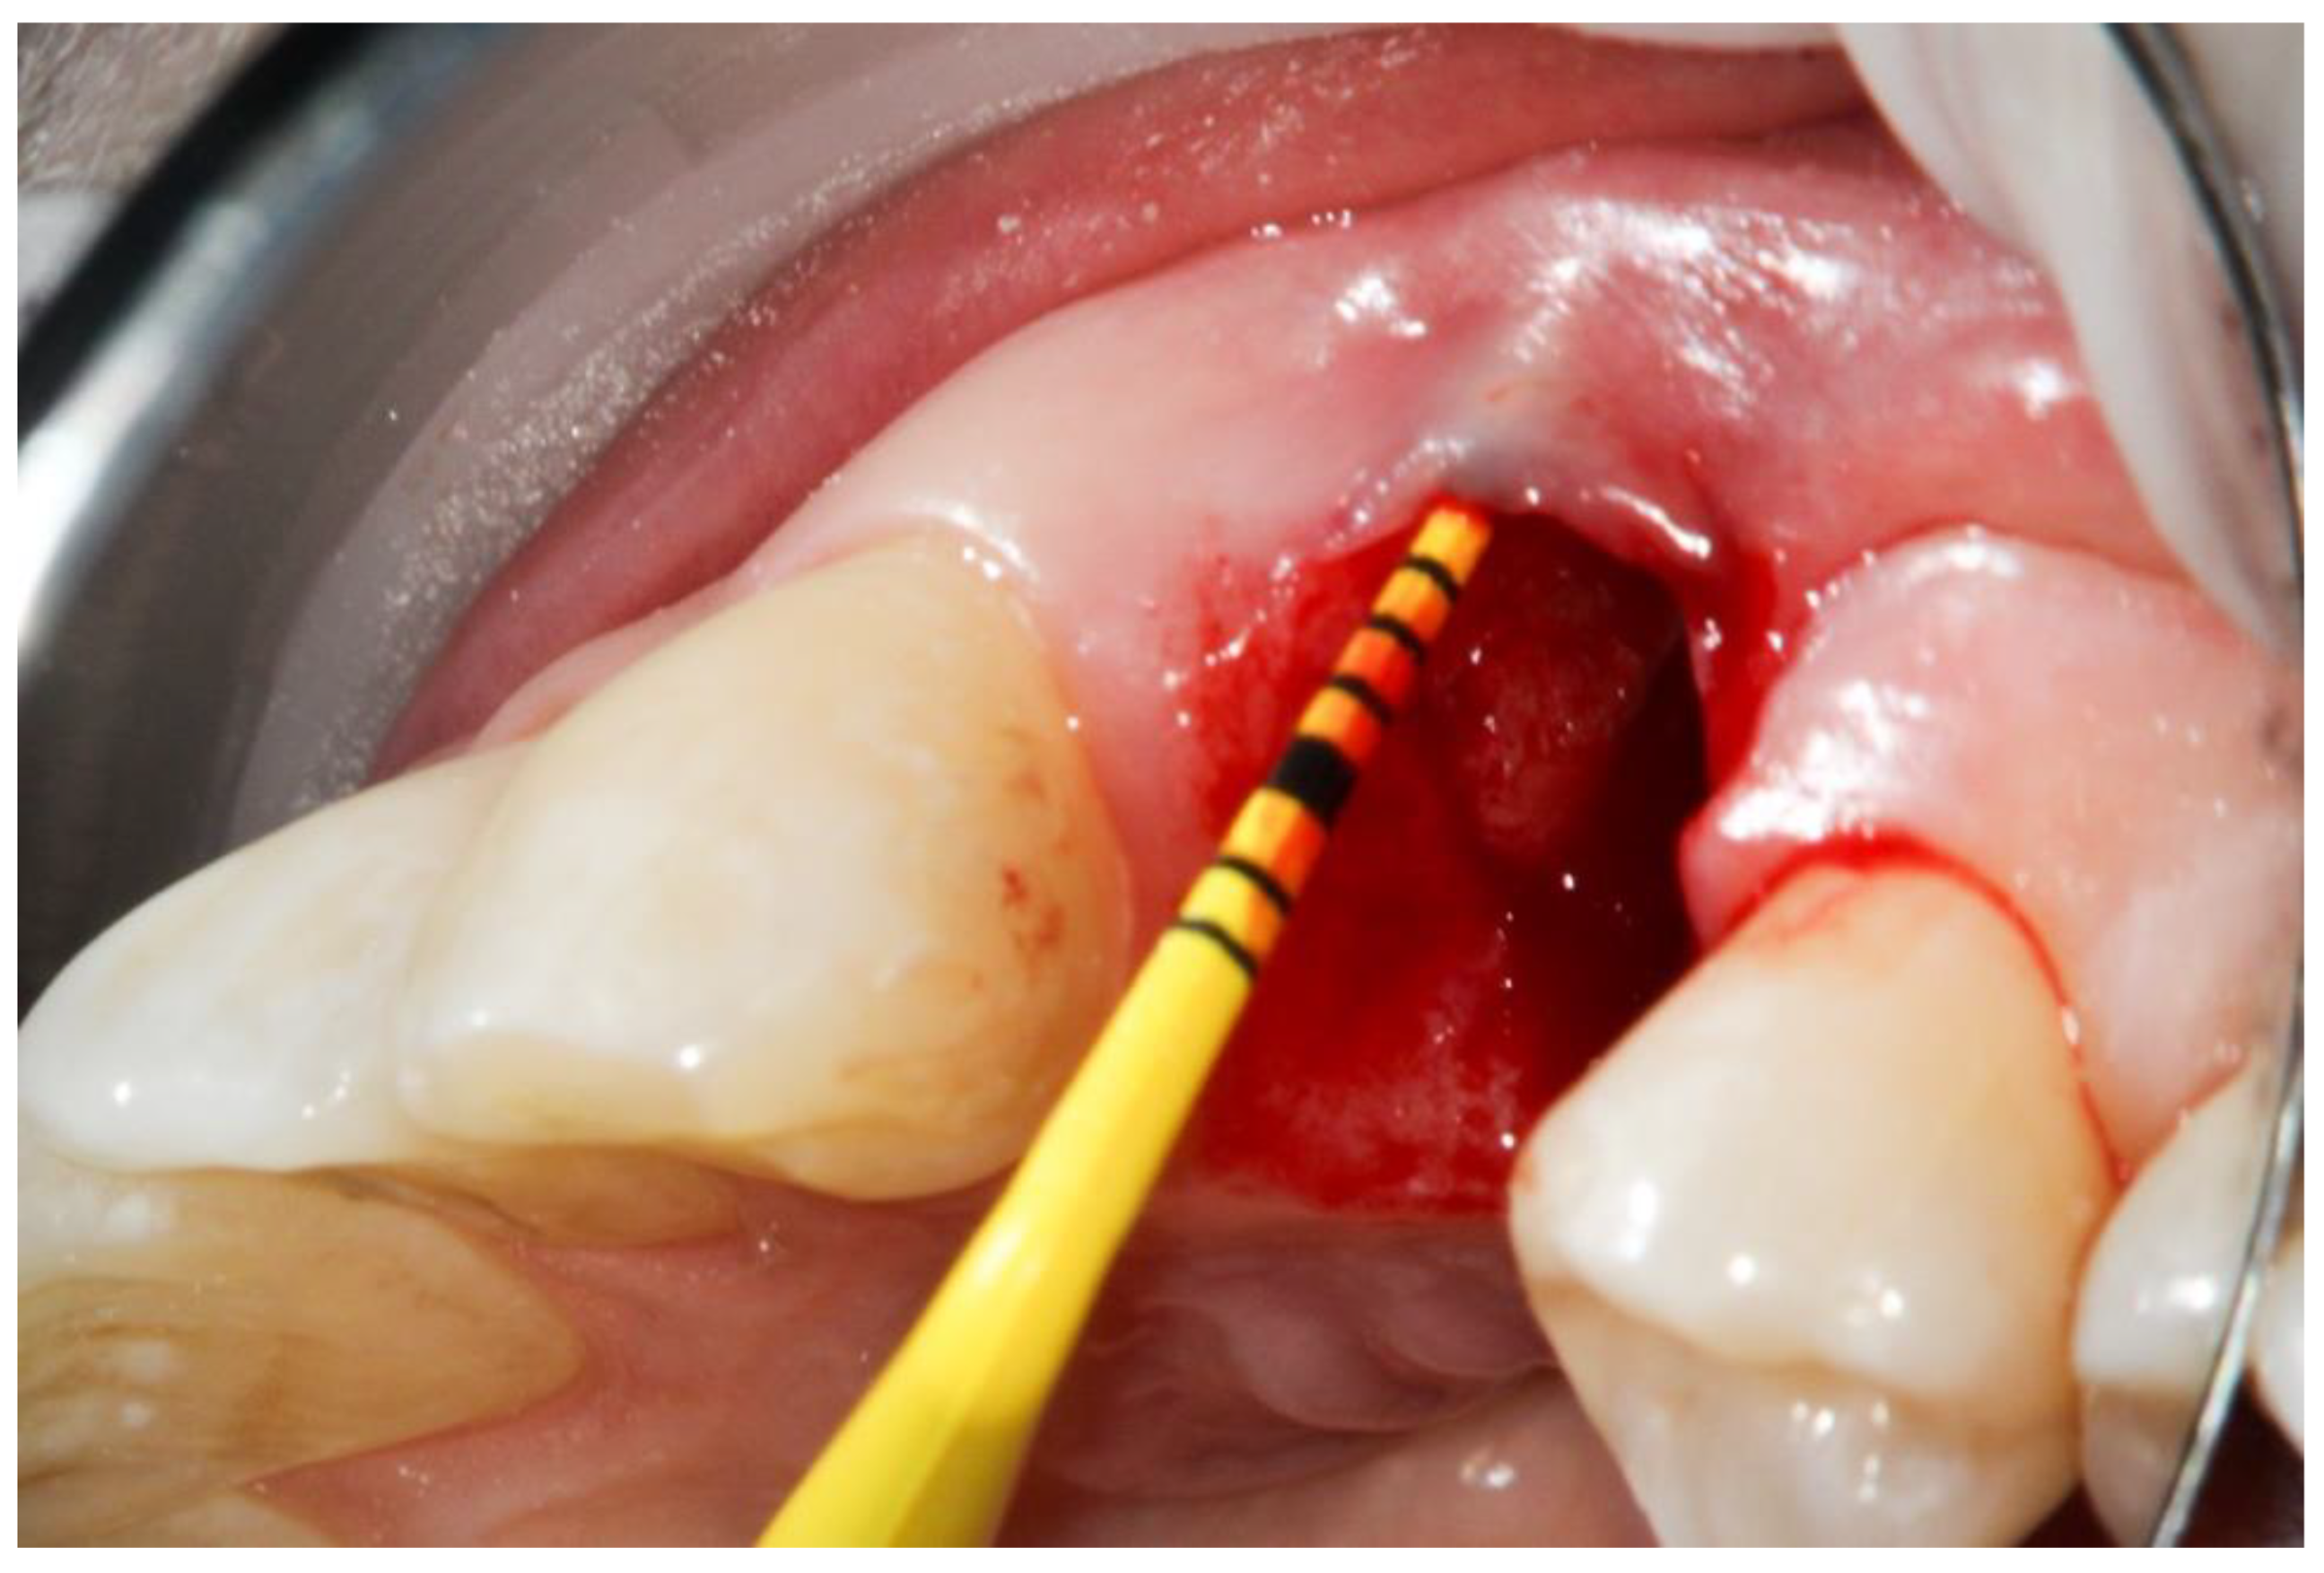

2. Materials and Methods